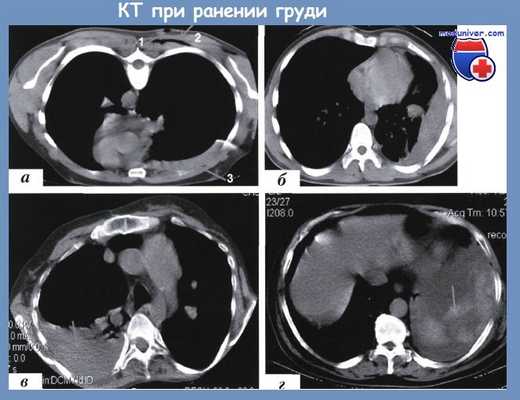

Спиральные компьютерные томограммы груди при гемотораксе различного объема